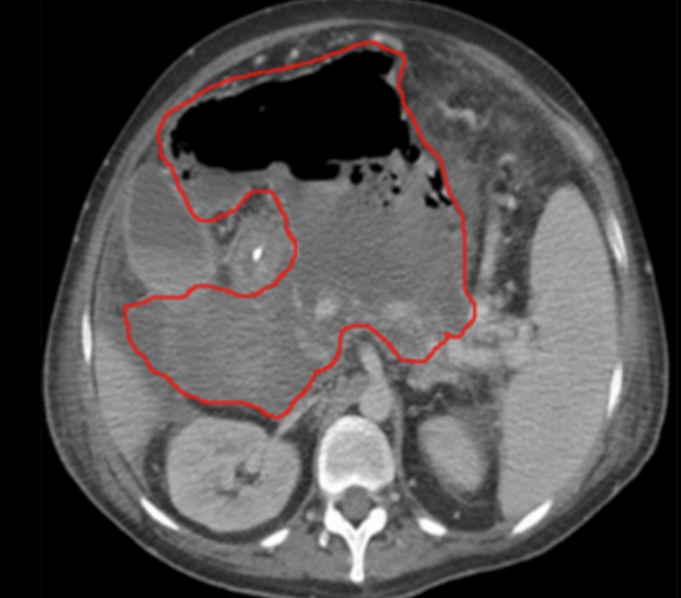

Source control

Occult subcutaneous abscess in cellulitis New abscess formation in intraabdominal infection Empyema in community-acquired pneumonia Visceral or skeletal abscess in patient with bacteremia Failure to remove a central venous catheter